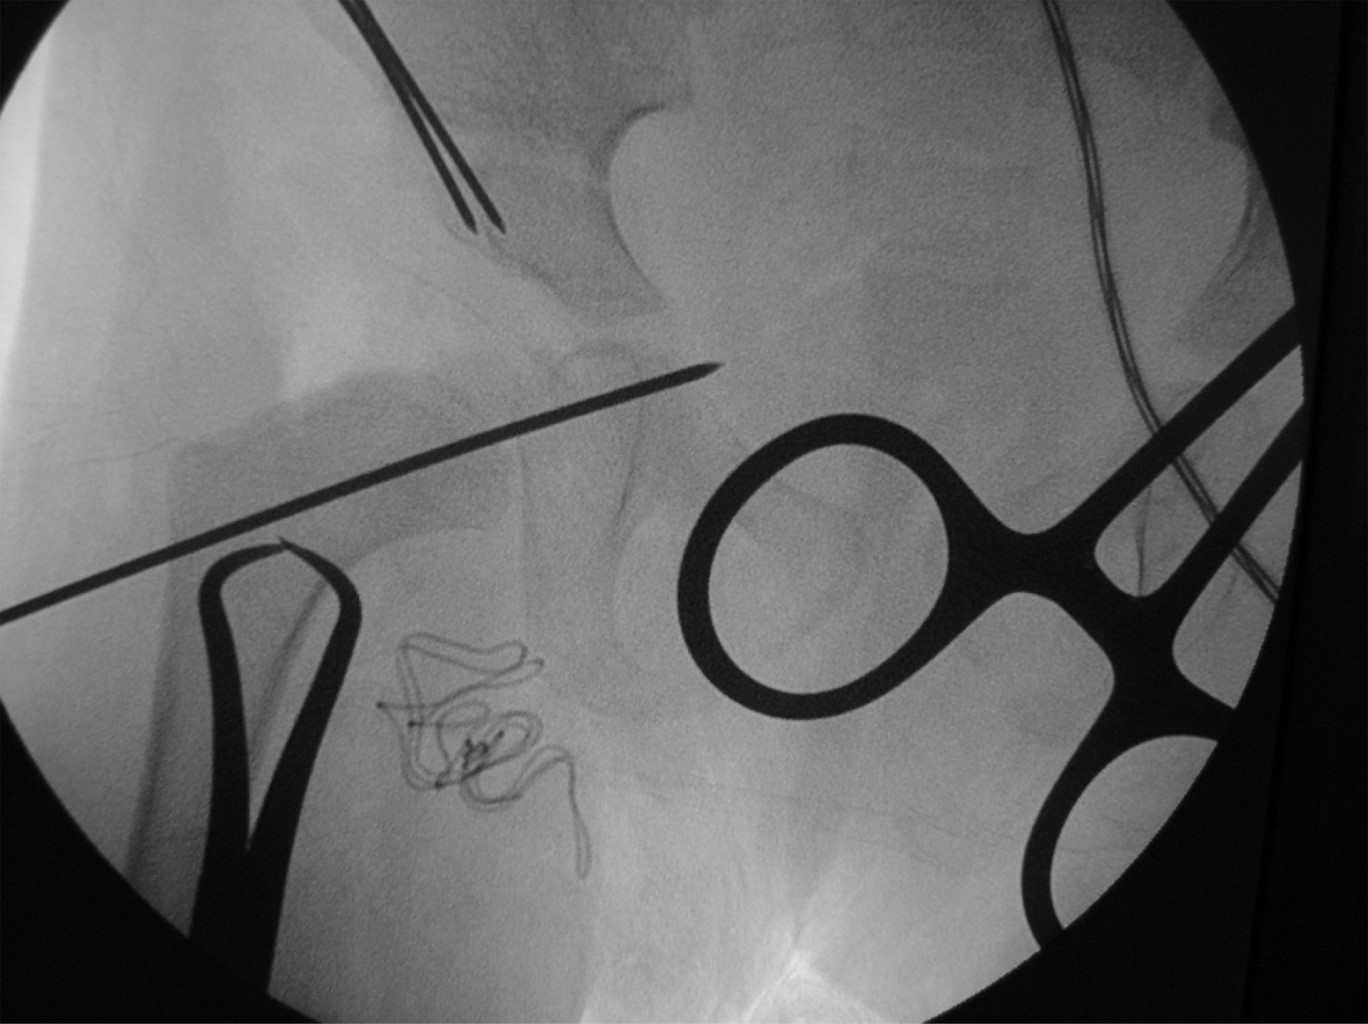

En todos los casos con DDC estudiados se les realizó miotomía de aductores con tenotomía del psoas por medio de abordaje medial transversal a nivel de la ingle; para la reducción de la cadera, se abordó por vía anterolateral y se realizó un abordaje tipo Smith-Peterson, se desinsertan el sartorio y el recto anterior, hasta visualizar lo más posible la cápsula articular y apreciar la parte más medial de la cápsula de la cadera; posteriormente, se realiza una fractura de la epífisis Salter tipo 1 a nivel de la cresta iliaca y se desperiostiza la cara interna y externa del iliaco hasta la escotadura ciática mayor. A continuación, se realiza una capsulotomía en "T" con liberación medial de la cápsula articular con resección del ligamento redondo, resección del ligamento transverso y pulvinal, evitando lesionar el cartílago articular del acetábulo y sin resección del labrum. Se reduce la cadera y se fija con un clavo Kirschner, dejándolo en el tercio medio o inferior del cuello femoral (Figura 1). Después, mediante un abordaje lateral a nivel femoral se realiza osteotomía varizante y desrotadora, esto último cuando hay más de 60o de anteversión, preservando de 15-20o de anteversión femoral y una diafisectomía de 8-10 mm como máximo para evitar una subluxación por tener cadera inestable; la osteotomía femoral se fija con una placa DCP de 3.5 mm con dos tornillos proximales y dos distales. Posteriormente se realiza osteotomía tipo Salter para mejorar la cobertura acetabular dirigiendo el extremo distal hacia la parte lateral y anterior para mejorar el índice acetabular y la cobertura lateral, colocando un injerto en "V" a nivel de la apertura de la osteotomía de Salter, fijando ésta con dos clavos de Kirschner, estas agujas no deben atravesar la superficie articular del acetábulo. Durante todos los procedimientos se toman imágenes de control con intensificador de imagen para valorar la reducción de la cadera, la osteotomía femoral y la osteotomía de Salter (Figura 2). En todas las caderas se realizó capsulorrafia en "V"; se reinsertan los músculos sartorios y el recto anterior en su porción directa y refleja, y se sutura la epífisis de la cresta iliaca con sus inserciones musculares respectivas. Finalmente, se coloca un aparato de yeso tipo Callot a 20o de flexión de cadera; 20o de abducción y ligera rotación interna, con flexión de rodillas, el cual se mantiene por seis semanas, tiempo en el que también se retira el clavo Kirschner y posteriormente se coloca aparato de yeso tipo Bachelor por seis semanas más.

Figura 2